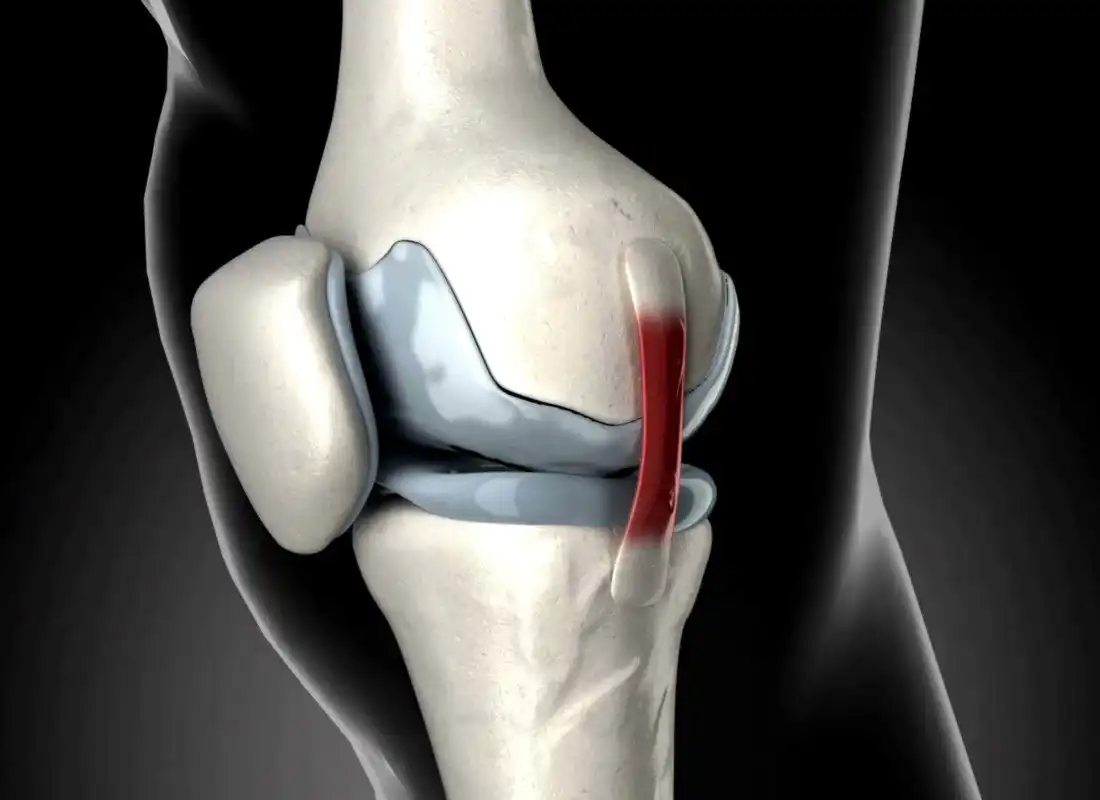

جدیدترین روش ترمیم رباط صلیبی زانو | آرتروسکوپی مدرن 1405 با کمترین درد و سریعترین بهبودی برای تمامی بیماران ادامه مطلب »